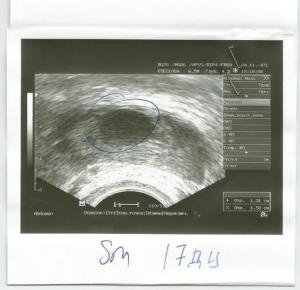

Овуляция( тесты на овуляцию)Добрый день! Помогите кто может разобраться! Сегодня 23 день цикла. Планируем ляльку. 7 месяцев назад была ВБ, удалили правую трубу. Сейчас как раз заработал левый яичник. На 10 ДЦ врач на УЗИ увидела два доминантных фолликула - 12 и 15 мм. Пришла повторно через неделю на 17-й день! И уже увидела только один и всего 13 на 15 мм. И остальные маленькие по 5-6 мм. Куда делся второй неизвестно. Сказала - овуляции наверное уже не будет. Потому что растет медленно очень. Я расстроилась невозможно. Так надеялись на этот цикл. БТ я мерить стала в этом цикле только дня с 15-го по-моему. И непонятно почему она стала подниматься с 16 дня. Опустилась на пару дней до 36,5 три дня назад. И низ живота сильно тянуло в этот день. Я испугалась и вчера помчалась опять на УЗИ. И она была крайне удивлена, глянув в монитор. У меня исчез и этот филликул. НЕТ ЕГО И ВСЁ! И жт не видно. Вчера сдала прогестерон 36,29. Норма в этой лаборатории до 27. Позавчера еще ТТ поднялась, 37,0. Держалась два дня. Насморк сильный и глаза слезились. Сегодня получше. Что со мной может быть?! Буду рада всем советам и поддержке!